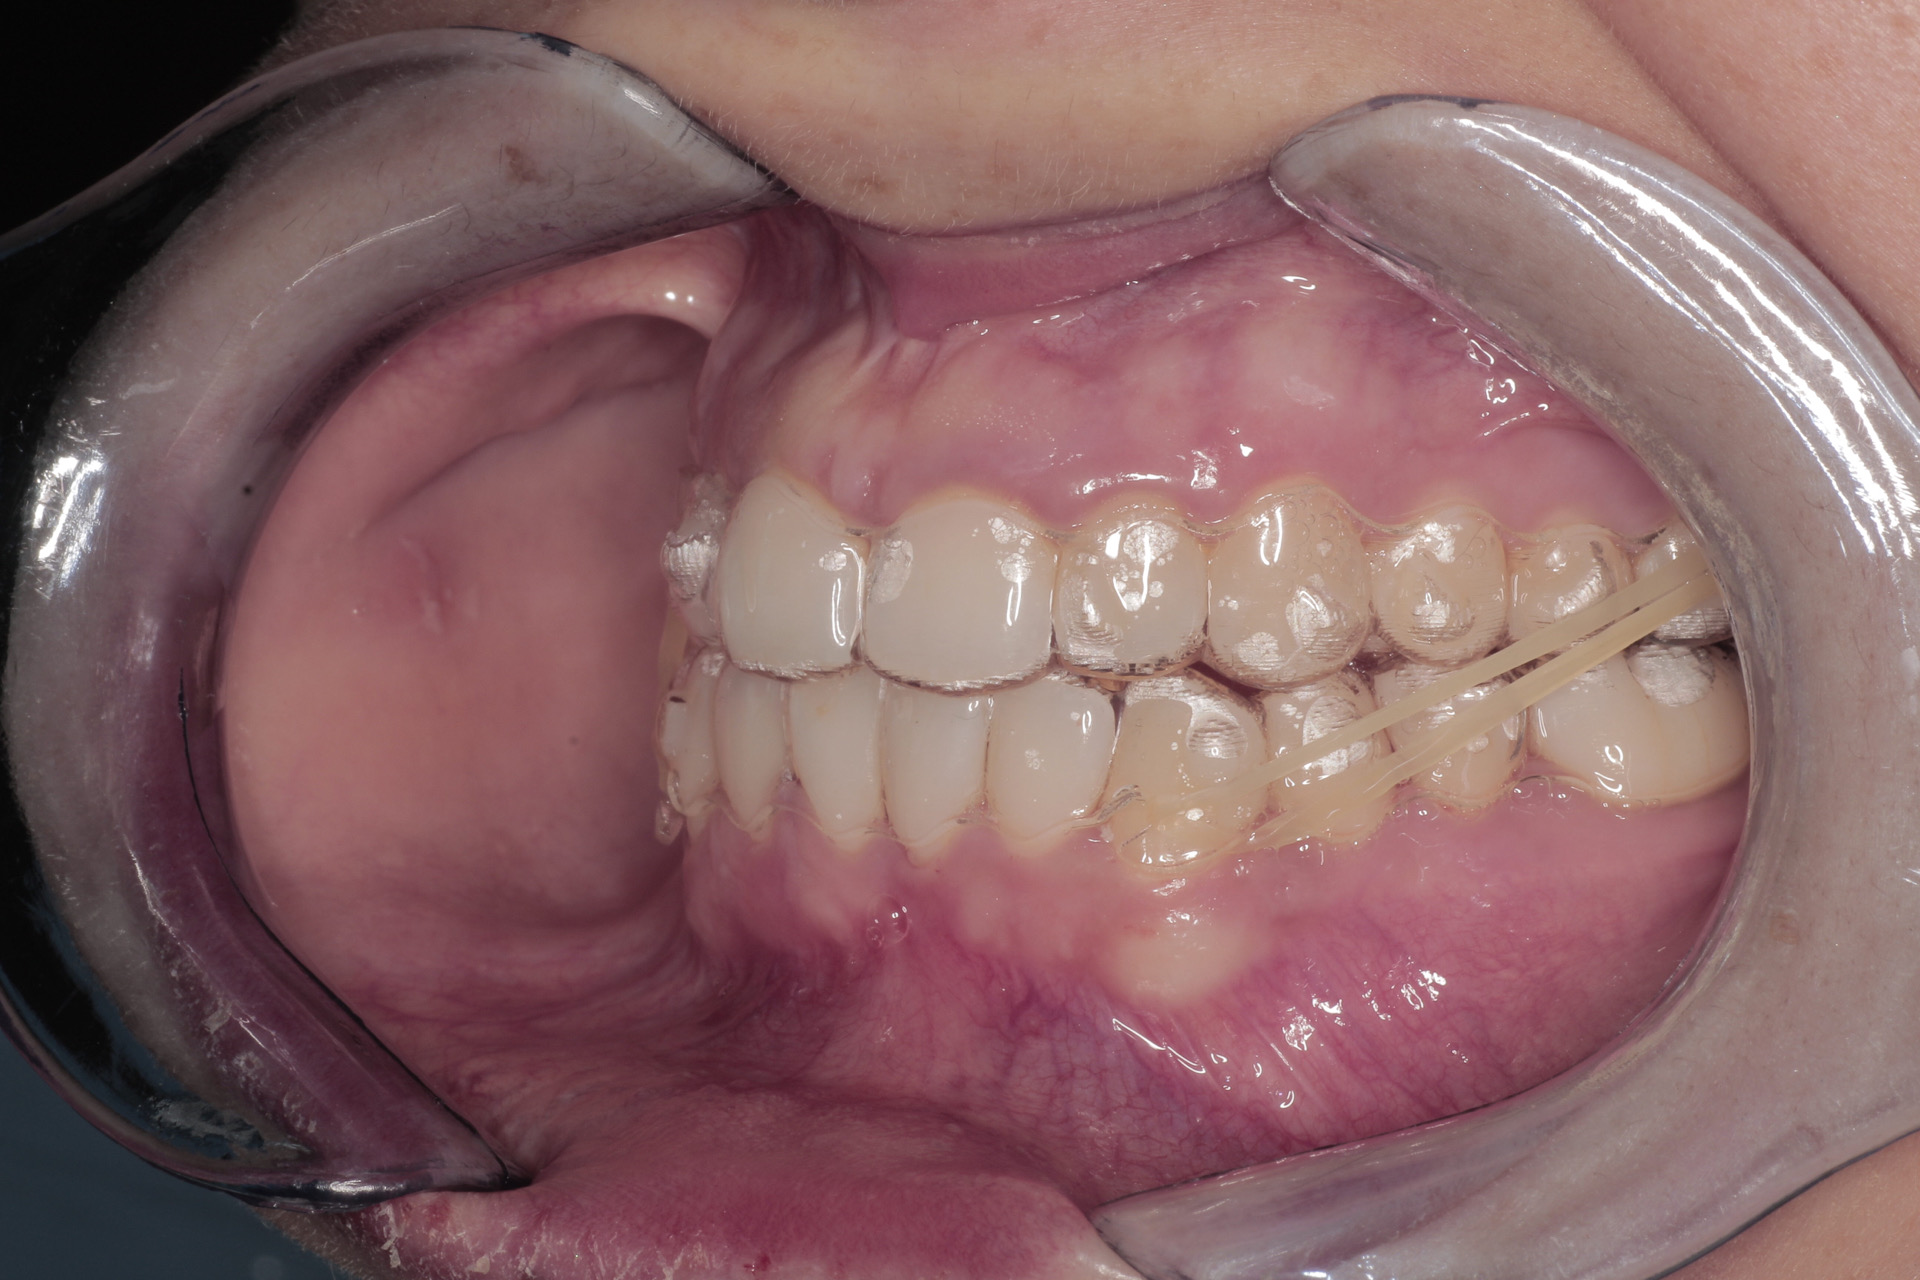

• La progettazione di una o più serie di allineatori costituiti da materiali brevettati INVISALIGN in grado di trasferire forze in tempi ed intesità specifiche che il paziente dovrà cambiare seguendo le indicazioni dello specialista. In alcune situazioni verranno inseriti piccoli attacchi in resina, poi rimossi a fine trattamento, per aiutare gli allineatori ad eseguire anche i movimenti più difficili.

• Posizionamento degli attachment : piccoli pezzi di resina bianca incollati su alcuni denti necessari per controllare le forze ed eseguire alcuni movimenti.